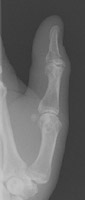

- Click on the image for a larger versionBPA and oblique radiographs of the hand. The also show the fracture of the fourth proximal phalanx.